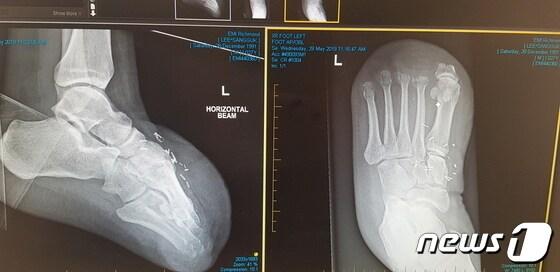

본문 이미지 - 이상국씨 발가락 절단 엑스레이 사진(이상국씨 제공) ⓒ 뉴스1

이상국씨 발가락 절단 엑스레이 사진(이상국씨 제공) ⓒ 뉴스1